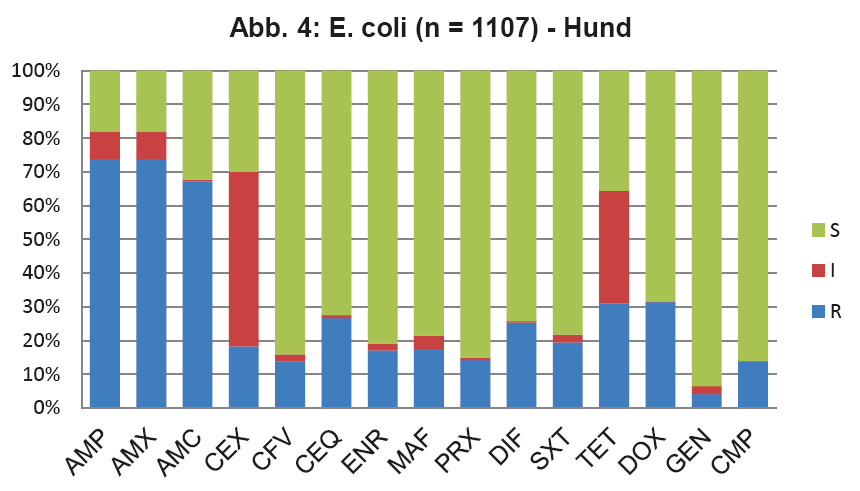

- Abb. 4: E. coli (n = 1107) – Hund

Die vier wichtigsten Keime bei der Katze sind E. coli, Staphylokokken (koagulasepositive und -negative) und Enterokokken. Diese machen zusammen sogar 77% der Nachweise aus. Um nun zu überprüfen, ob die in den ISCAID Richtlinien vorgeschlagenen Wirkstoffe für eine empirisch ausgesuchte Ersttherapie auch für unsere Verhältnisse Gültigkeit haben, muss man die Resistenzmuster dieser Keime einzeln überprüfen. Die Darstellung dieser Daten würde den Umfang eines LABOKLIN aktuell sprengen. Daher geben wir hier exemplarisch die wichtigsten Keime wieder. Abb. 4 zeigt die Resistenzverteilung von E. coli bei HWI vom Hund, die Verhältnisse bei der Katze sind ähnlich.

Für die Ersttherapie werden nach ISCAID Richtlinien AMX und SXT vorgeschlagen, wobei AMX der Vorzug gegeben wird. In vielen europäischen Ländern ist AMX sehr gut wirksam gegen E. coli. Dies ist offensichtlich bei uns nicht der Fall (s. Abb. 4). Bei unklarer Keimzusammensetzung wäre daher SXT nach unserer Datenlage für die Ersttherapie der Vorzug zu geben. Auf ENR sollte zunächst aus den oben genannten Gründen verzichtet werden. Es wird noch als Reserveantibiotikum für wirklich schwierige Infektionen benötigt. Wenn im Harnsediment eine Unterscheidung in Kokken und Stäbchen erfolgt, kann man bei Vorliegen von Kokken gut mit AMX als Ersttherapie arbeiten (s. Abb. 5 + 6). Es muss bedacht werden, dass die uns vorliegenden Daten die eigentliche Resistenzlage zu hoch wiedergeben könnten, da häufig erst bei Therapieversagen eine BU eingeleitet wird. Somit könnte die Resistenzlage für AMX in der Praxis besser sein, als hier dargestellt. Darüber hinaus reichert sich AMX im Urin stark an.